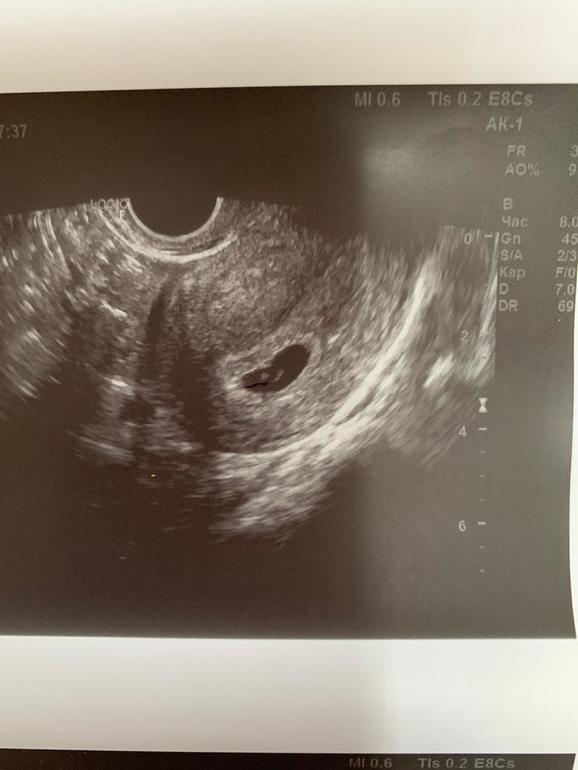

Наше первое узи

По узи 5недель 5 дней по месячным 6,3 сердцебиение есть, эмбриончик видно 😍